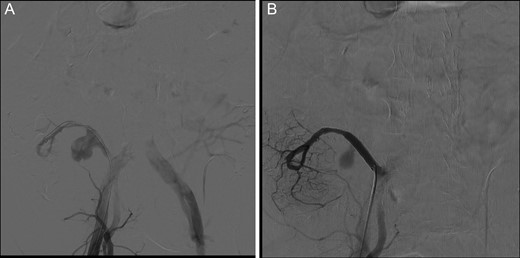

Whilst on the waiting list for this elective procedure, the patient was urgently admitted to a teaching hospital >1 hour away with acute hemodynamic instability. He was suffering from gastrointestinal haemorrhage after an overdose of vitamin K antagonists (International Normalized Ratio > 9), with a possible arterio-enteric fistula. An emergency angiography was performed and the large aneurysm identified (Fig. 3A). No blush was seen nor contrast in the splenic artery. A metal covered stent (Viabahn6 mm in diameter, length of 50 mm, Gore Medical, Tilburg, Netherlands) was placed covering in the Y graft and graft superior mesenteric artery (SMA), covering the origin of the splenic artery but ensuring adequate perfusion of the pancreas head (Fig. 3B). The patient was transferred to our Transplant Center and remained stable during several days of observation. CT angiography showed obstruction of the splenic artery, but a well perfused pancreas. Function remained excellent.

(A) Emergency angiography showing increased Y graft aneurysm. The splenic artery is not perfused. (B) Stent placed through the Y graft and SMA, covering the aneurysm and origin of the splenic artery.